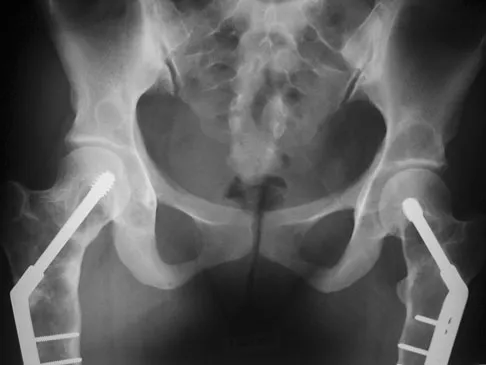

A patient with rheumatoid arthritis with both ankle and subtalar involvement was treated as shown in Figures 11a and 11b. What complication is unique to this type of fixation?

Explanation

The interlocking screws at the proximal end of the rod can act as a stress riser and lead to fracture. Postoperative pain at this level should prompt inclusion of this diagnosis in the differential. Removing the screws following bone union can decrease the chances of this occurring. A short rod that avoids the diaphyseal area may also be beneficial. Rotatory deformity is controlled by the perpendicularly oriented distal transfixion screws. Talar osteonecrosis would be unusual since the dissection can be minimized with an intramedullary rod. Any type of hardware can fail if the construct does not lead to a solid arthrodesis. Nunley JA, Pfeffer GB, Sanders RW, et al (eds): Advanced Reconstruction: Foot and Ankle. Rosemont, IL, American Academy of Orthopaedic Surgeons, 2004, pp 236-237. Thordarson DB, Chang D: Stress fractures and tibial cortical hypertrophy after tibiotalocalcaneal arthrodesis with an intramedullary nail. Foot Ankle Int 1999;20:497-500.